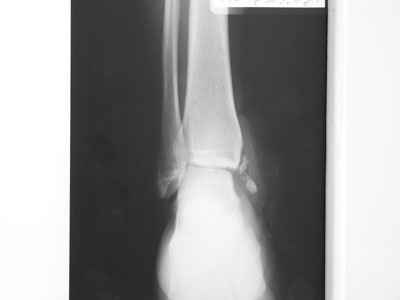

Уважаемые коллеги! Прошу прощения за собственную невнимательность. У больной травма не 1 января 2011г., а 1 декабря 2010г., т.е. уже 2 месяца.

Прилагаю данные фистулогрфии. Основной вопрос, все же, лечить консервативно или оперативно? Если оперативно, то какой объем? А что если прийдеться резецировать всю медиальную лодыжку!?

С уважением Александр Белоконь!